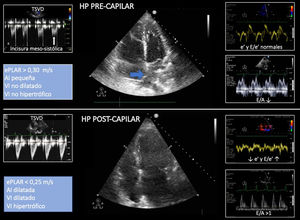

Hipertensión pulmonar precapilar vs. poscapilarLa causa más común de fracaso del VD es la HTP definida como PAPm≥25mmHg29. El análisis de la IT permite estimar HTP, VmaxIT≤2,8m/s se asocian con una baja probabilidad de HTP, mientras que VmaxIT>3,4m/s se asocian con una alta probabilidad de HTP (fig. 5).

Algoritmo para determinar la probabilidad de presentar hipertensión pulmonar mediante ecocardiografía. a Necesaria la presencia de signos de al menos 2 categorías. b Colapso <50% con la inspiración forzada, <20% con inspiración normal. AD: aurícula derecha; AP: arteria pulmonar; HP: hipertensión pulmonar; PAPs: presión sistólica de la arteria pulmonar; TAPSE: excursión sistólica del plano del anillo tricuspídeo; TSVD: Tracto de salida del ventrículo derecho; VCI: vena cava inferior; VD: ventrículo derecho; VI: ventrículo izquierdo.

Diagnosticar la causa de la HTP es de vital importancia al determinar el tratamiento adecuado. En este sentido, un primer paso debe diferenciar si la causa es precapilar, presión capilar pulmonar (PCP) ≤15mmHg o poscapilar debido a patología del VI, PCP≥15mmHg. Los hallazgos ecocardiográficos que sugieren una etiología pre- o poscapilar se describen la figura 629. El cálculo de las RVP ayuda en su diferenciación30.

Signos sugestivos mediante ecocardiografía de hipertensión arterial pulmonar pre- y poscapilar. La flecha azul señala el septo interauricular abombado hacia la aurícula izquierda. AI: aurícula izquierda; ePLAR: ecocadiographic pulmonary to left atrial ratio=[VmaxIT/(E/e’) mitral]; HP: hipertensión pulmonar; TSVD: tracto de salida del ventrículo derecho; VI: ventrículo izquierdo.

Un parámetro invasivo que ha demostrado ser útil en la diferenciación de la HTP pre- y poscapilar es el gradiente transpulmonar definido por la diferencia entre la PAPm y la presión de la AI, estimada por la PCP45. Un valor superior a 12mmHg indica un origen precapilar. Recientemente, se ha sugerido que un indicador sustito del gradiente transpulmonar sería la relación ecográfica pulmonar/AI (ePLAR) medido por la relación entre la VmáxIT, como estimado de la presión pulmonar y la relación E/e’ mitral, como estimado de la presión de AI. Valores de ePLAR>0,30m/s serían indicativos de HTP precapilar y <0,25m/s de poscapilar45.